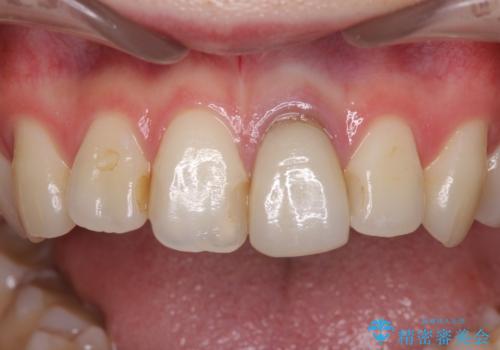

- 前歯のクラウン付近の歯肉が黒く見えることを気にして来院された患者様です。

根管治療を行った後に、オールセラミッククラウンにて補綴することとしました。